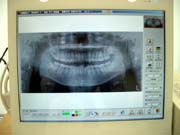

【デジタルレントゲン】

当院のレントゲンは、従来型のものと比べ、通常のデジタル撮影で被曝量を1/10と大幅に軽減しております。

又、パノラマ撮影でも従来型よりも被曝量が少ないものとなっております。

現像の際に廃液が出ることもなく、環境にも優しいものとなっております。

撮影させて頂いたレントゲン画像は、チェアーの目の前のパソコン画面にて鮮明な画像をご覧いただけます。